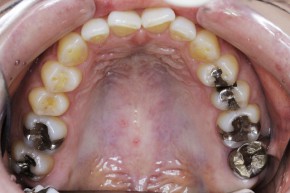

| 治療内容 | 左上7の不適合メタルクラウンを新製。 元々入っていたメタルコアをファイバーコアに作り直し、形成印象したのちエステニアクラウンをセット |

左上7の金属のかぶせ物の不適合が見受けられました

金属の一部が欠けておりこのままですとここから虫歯になってしまいます